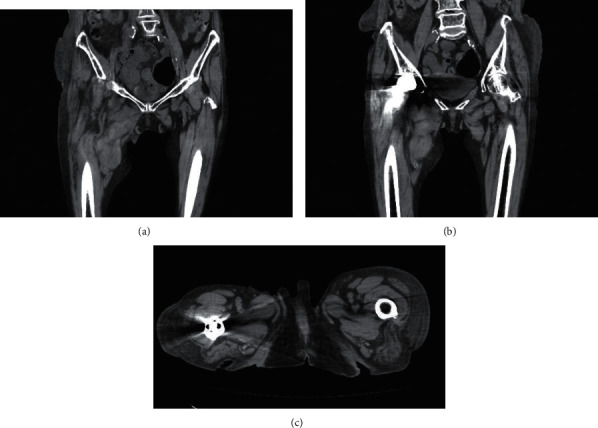

Background: When an obturator nerve block (ONB) is performed, the conventional landmark method or ultrasound-guided method is used. The major complications of this block are hematoma, but there are very few reports of its complications. We encountered massive bleeding and a huge hematoma after ONB. Case Presentation. A 95-year-old female underwent transurethral resection of the bladder tumor. Induction of anesthesia was accomplished via spinal anesthesia and right ONB using the landmark method. Postoperatively, subcutaneous bleeding was detected in the lower right interior thigh. Concentrated red cell transfusion was conducted to address the anemia. There was no subsequent expansion of the hematoma. It resolved on postoperative day (POD) 53. The hematoma was deemed to be inadvertently introduced due to an obturator artery puncture during the obturator nerve block.

Conclusions: Close attention is necessary to avoid advancing the needle too deep into the obturator during obturator nerve block.